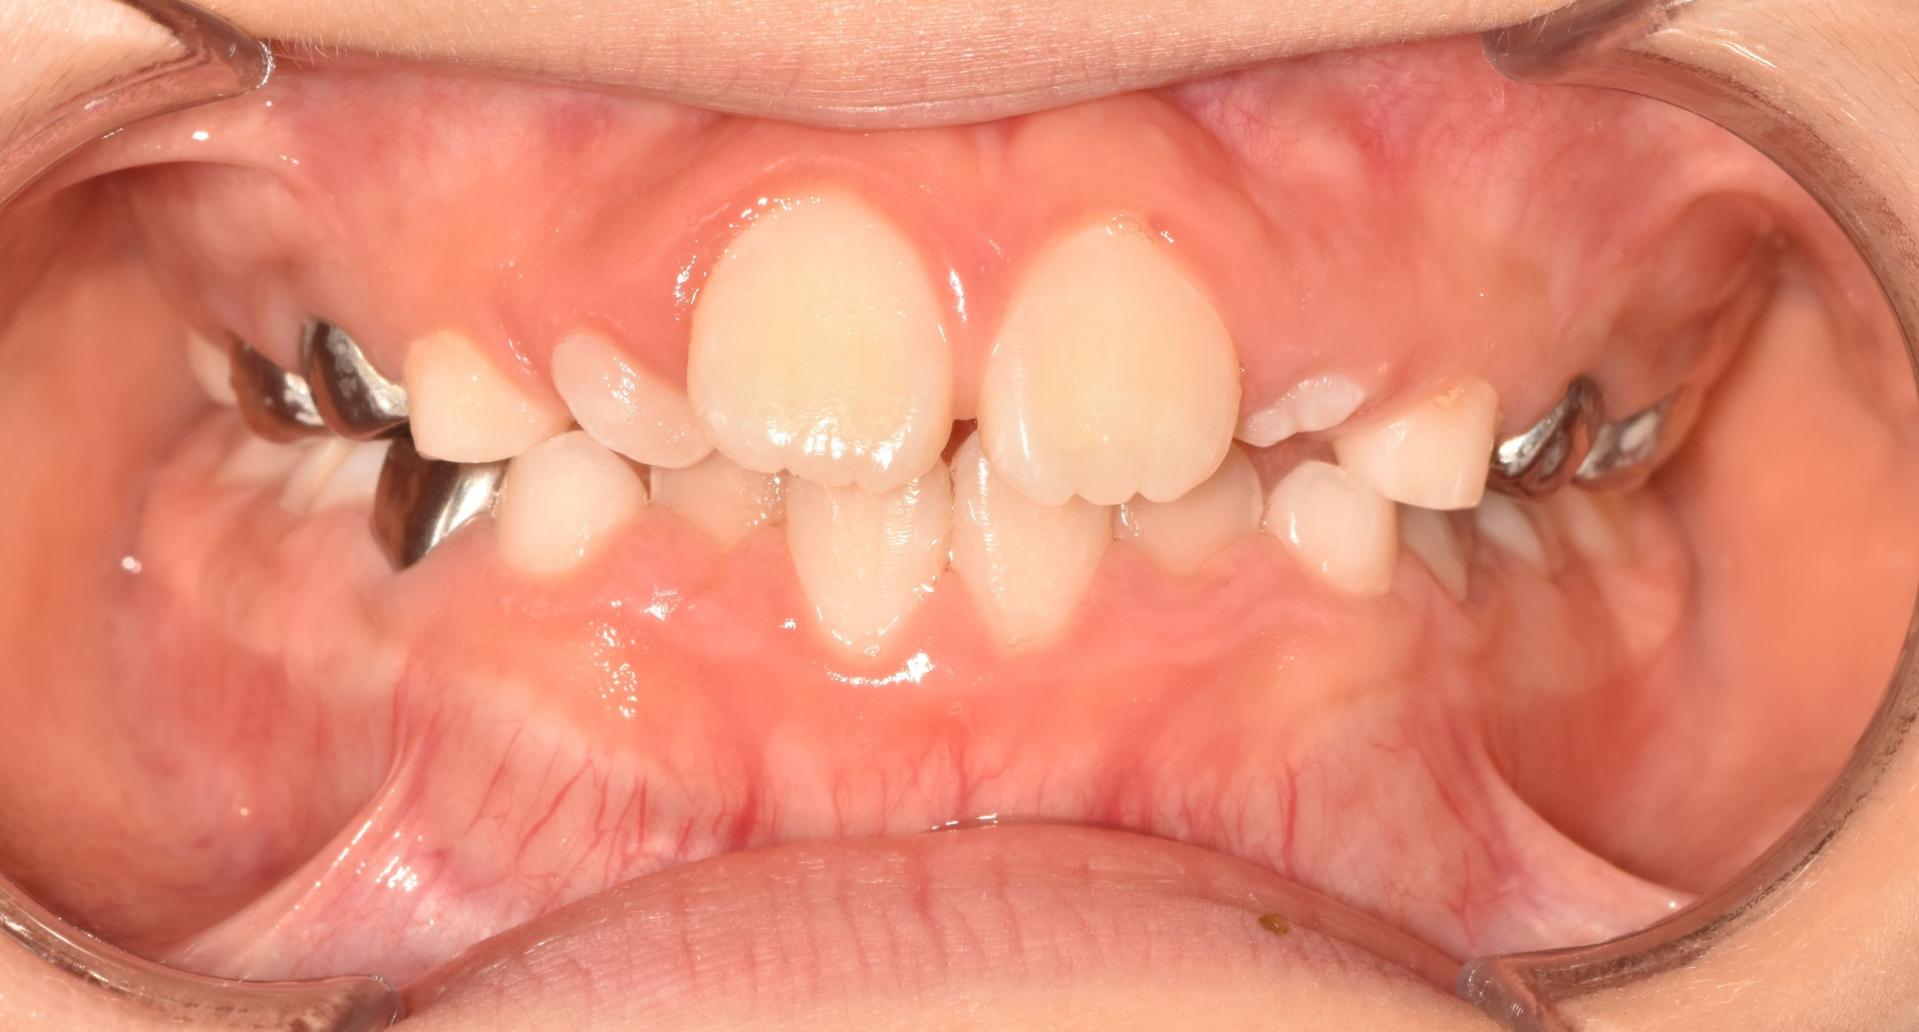

초진상태 입니다. 치아가 나올 공간이 부족하여 치아가 회전되어 삐뚤빼뚤나오고 앞니가 튀어나와있습니다.